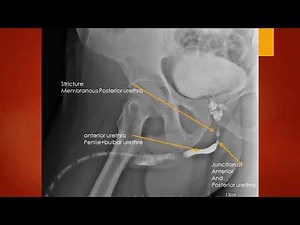

A retrograde urethrogram (RUG) is a diagnostic x-ray procedure used to visualize the urethra, often to evaluate for urethral injuries, strictures, or other abnormalities, by

Dr. Muhammed Ziya. . A retrograde urethrogram (RUG) is a diagnostic x-ray procedure used to visualize the urethra, often to evaluate for urethral injuries, strictures, or other abnormalities, by injecting contrast dye into the urethra and taking x-rays. . www.drmuhammedziya.com . 👉Follow NEW page Health 4 all for more medicine and nutrition ...

Retrograde Urethrogram (RUG)! A detailed look at the male urethra — from the urinary bladder all the way to the fossa navicularis 👇 This image beautifully demonstrates the continuity and anatomy of the urethral tract, crucial for evaluating urethral strictures, trauma, or post-surgical assessments. 💡 #RadiologyBuzz 🧠 #RetrogradeUrethrogram #RUG #UrethraAnatomy #MaleUrethra #Radiology #MedicalImaging #Xray #ContrastStudy #DiagnosticRadiology #RadiologyLife #Radiographer #Urology #UrethralStric